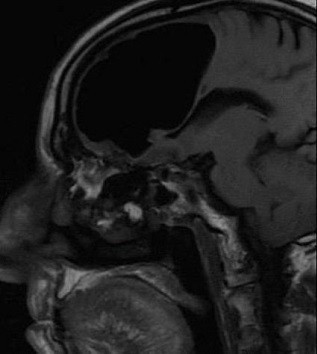

Galerinin tamamı için tıklayınızİRLANDA'da doktorları şaşkına çeviren bir tıbbi gelişme yaşandı. Haberin başrolünde baş ağrısı şikayetiyle hastaneye giden 84 yaşındaki yaşlı bir adam var. Adam hastanede beyinsiz olduğunu öğrendi. Peki nasıl bir insan beyni olmadan yaşayabilir? Doktorlar bu vakadan sonra, bu sorunun yanıtına cevap aramaya başladı. İşte ilginç olayın ayrıntıları.